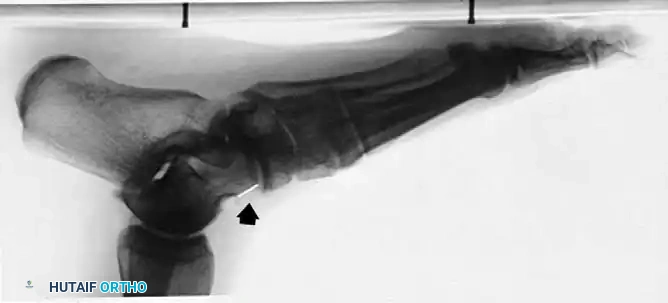

On the lateral weight-bearing film, the talonavicular, cuneiform–first metatarsal, and dorsal alignments must be closely examined. A "sag" at any of these joints indicates a critical loss of structural integrity in the medial column.

Fig. 79-9 C, Note “sag” at talonavicular joint (arrow) in the symptomatic left foot.

Fig. 79-9 D, There is no sag in the asymptomatic right foot.